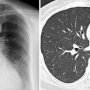

咳や痰が続きつらいなら疑うべき…「気管支拡張症」とは?

「長引く咳」に悩んでいるようなら、もしかしたら気管支拡張症かもしれない。近年、欧米では一度忘れられかけたこの病気に注目が高まっている。JCHO東京山手メディカルセンター呼吸器内科の徳田均医師に聞いた。 風邪が治っても咳や痰がい...